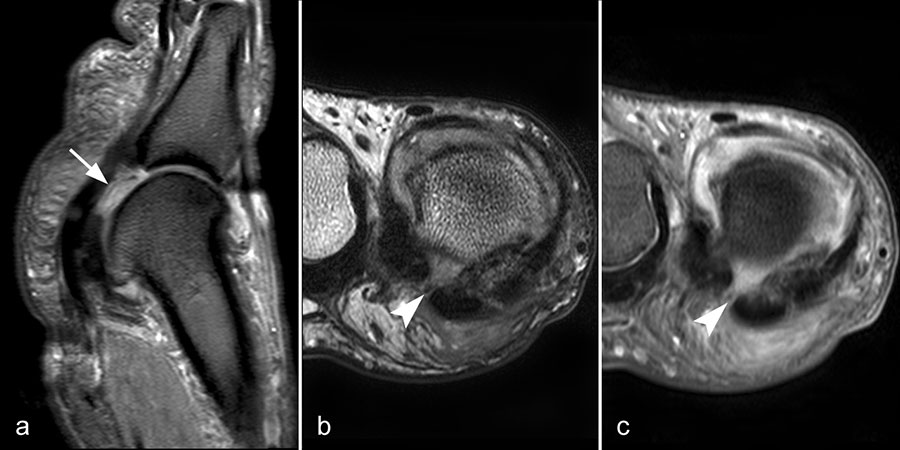

Gicht

Typische Gichtmanifestation an der Großzehe mit Tophusstachel (Pfeil) und großem Tophus, in welchem Uratablagerungen identifiziert werden können (Pfeilspitze). T1-gewichtete Sequenz vor (a) und nach (b) Kontrastmittelgabe, letztere mit Fettsuppression.

Dies erst recht, wenn diese Arthritis am Großzehen­grundgelenk auftritt (Abb. 15). In diesen Fällen sollte man den Verdacht auch dann aufrechterhalten, wenn die MRT nur eine unspezifische Entzündung zeigt und die Harnsäurewerte, die starken Schwankungen unterliegen können, nicht erhöht sind.

Spezifische MR Befunde finden sich erst bei der chronischen Gicht, wenn sich in T2 sehr signalarme Kristallablagerungen und Gicht-Tophi bilden. Letztere führen dann häufig zu den aus der Röntgendiagnostik bekannten gelenkfernen Erosionen.

Abbildung 15: Typische Gichtmanifestation an der Großzehe mit Tophusstachel (Pfeil) und großem Tophus, in welchem Uratablagerungen identifiziert werden können (Pfeilspitze). T1-gewichtete Sequenz vor (a) und nach (b) Kontrastmittelgabe, letztere mit Fettsuppression.